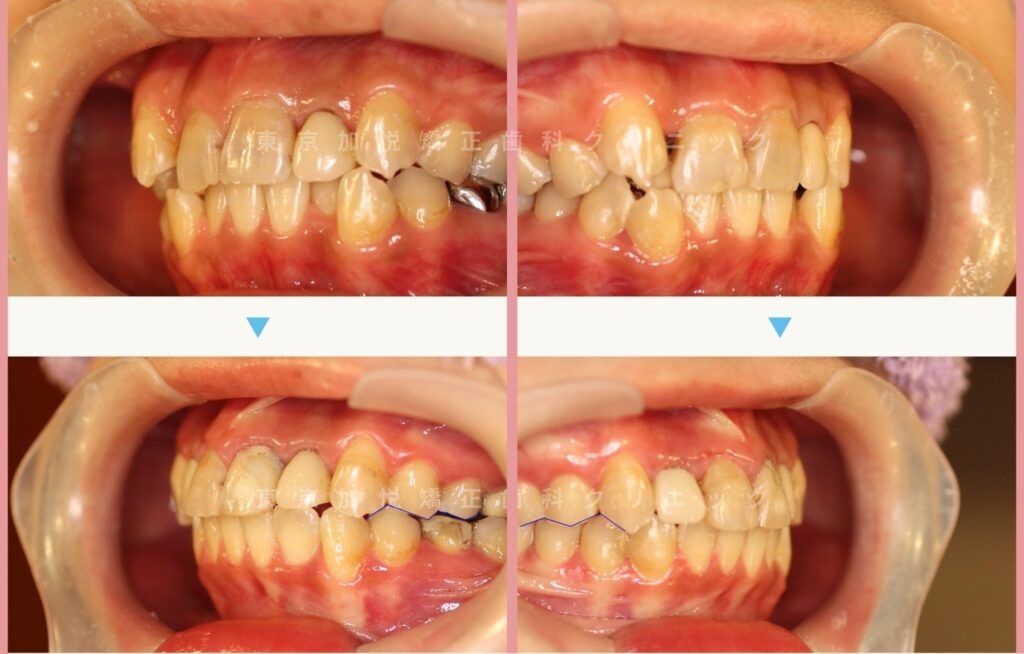

▼写真左:正面写真。歯ぐきと歯の間に目印

写真右:正面やや下方からの写真。歯の切端に目印

▼サイドからみら治療前後写真。写真内青線の部分が1歯に対して2歯で咬み合うようになり、奥歯の噛み合わせも大きく改善されました。

▼写真内にある目印の位置関係のバランスがとれ、審美的に大きく改善されました。前歯のかさなりももちろんとれ、清掃性が高まりました。